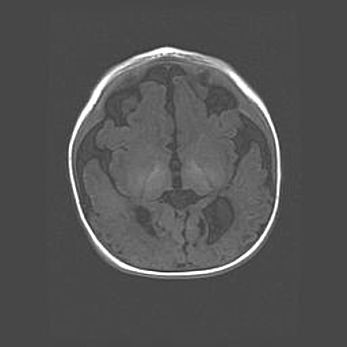

Наружная гидроцефалия с возможной атрофией височных областей.

Возраст: 28 дней

Вес: 3670 г

Пол: мужской

Окружность головы: 38 см

Срок гестации: 40 недель

Гидроцефалия головного мозга у новорожденных – это заболевание, которое характеризуется скоплением избыточного количества спинномозговой жидкости в желудочковой системе головного мозга в результате затруднения её перемещения от места выработки к месту поглощения в кровеносную систему или вследствие нарушения абсорбции. При открытой наружной форме гидроцефалии у новорожденных расширяются и переполняются субарахноидные пространства.

При нормотензивных  формах,  которые,  как  правило,  являются  следствием  перенесенных ишемических  повреждений  паренхимы  мозга,  возможно  сочетание микроцефалии  с нормотензивной гидроцефалией. В основе данных изменений лежит атрофия больших полушарий с преимущественной  локализацией  в  лобно-височных  областях.